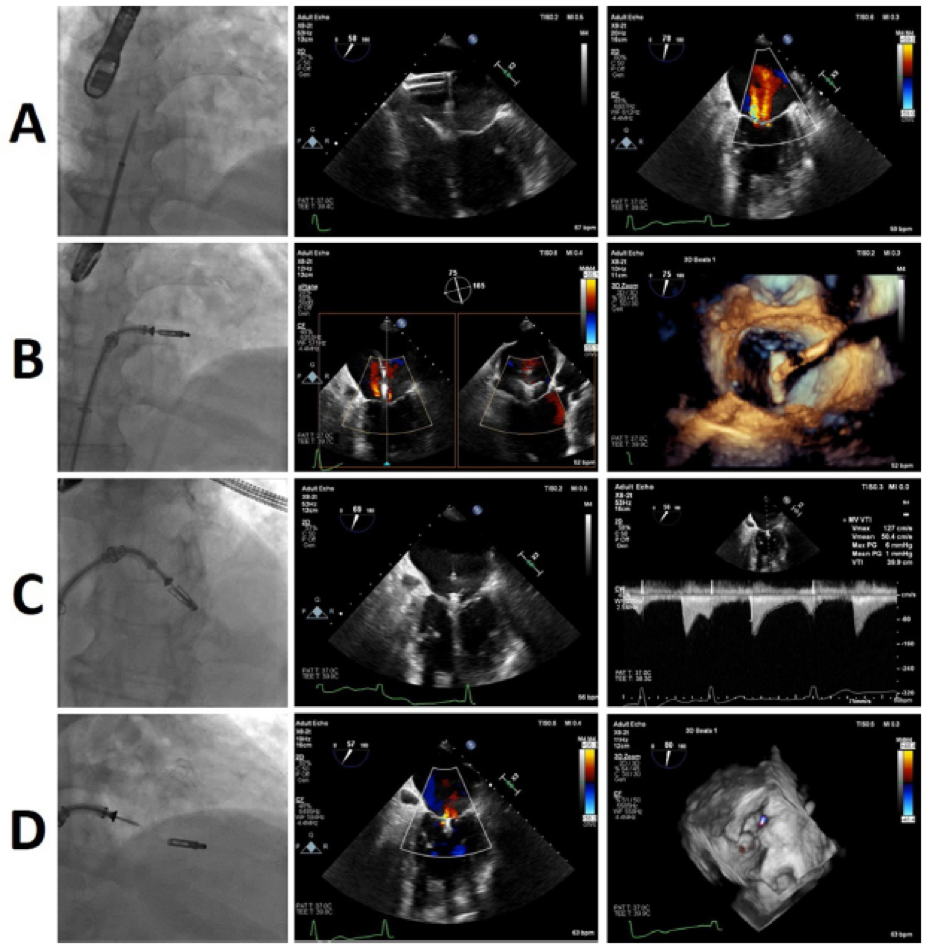

除MitraClip外,还有大量二尖瓣修复装置处于不同的开发阶段和监管批准阶段。这些器械通常处理外科修复过程的一个方面,无论是瓣环成形术、瓣叶或腱索修复,然而已经开展了组合修复手术(图7和图8)。虽然这个列表并不详尽,但它包括了主要的竞争者,重点是技术和可用的临床结果(图9)。

ero为什么不显示经导管二尖瓣修复术:相关病理生理学、研究和治疗综述_https://www.jmylbn.com_新闻资讯_第9张

图7:一名80岁男性退行性二尖瓣返流患者经导管二尖瓣修复联合Amend和MitraClip装置治疗。

(A)术前彩色多普勒经食管超声心动图(TEE)显示严重MR。术中彩色多普勒经食管超声心动图(TEE)显示(B)瓣环成形术和(C)缘到缘修复术后MR显著降低。(D)透视显示Amend和MitraClip均已就位。

MR:二尖瓣返流;TEE:经食管超声心动图。

ero为什么不显示经导管二尖瓣修复术:相关病理生理学、研究和治疗综述_https://www.jmylbn.com_新闻资讯_第10张

图8:一名68岁男性患者使用Amend和NeoChord装置进行经导管二尖瓣修复。

(A)术前经食道彩色多普勒超声心动图显示严重二尖瓣返流。术中经食管彩色多普勒超声心动图显示(B)瓣环成形术和(C)腱索修复术后二尖瓣返流显著减少。LA:左心房;LV:左心室。

图10:经导管二尖瓣修复器械的透视图像。(A)Pascal。(B)Carillon。(C) Cardioband;(D)Amend与MitraClip联合使用。(E) IRIS与与MitraClip联合使用;(F) Mitrallign;

IRIS是一个用于经导管二尖瓣修复治疗(TMVr)完整的半刚性经皮中隔环缩系统。由镍钛合金制成,并通过24F引导导管引入,锯齿形环由一个框架组成,该框架与8个张力环相连,以实现最佳的中隔横径缩小,以及8个可独立于二尖瓣瓣环(MA)组织重新定位的锚定件(图10E)。该手术通过透视、经食管超声心动图(TEE)和心内超声心动图的同时指导下进行。

IRIS系统首次植入于2018年,据报道有7名患者早期使用了IRIS系统,其中4名患者接受了手术植入,3名患者接受了经中隔植入。在经导管组,所有3名患者在30天时,手术导致平均间隔外径减小39%,MR等级降低至<1,纽约心脏协会(NYHA)功能等级为I-II,并且没有与手术相关的并发症。所有手术残余房间隔缺损(ASD)采用Amplatzer封堵器封闭。使用Millipede IRIS系统对MR二尖瓣进行瓣环矫形是一项早期可行性试验,已在巴西和巴拉圭完成了21名患者的登记(NCT02607527)。

2016年获得CE认证的Mitrallign是一种经动脉环成形术系统,通过14F引导导管从股动脉逆向输送至二尖瓣瓣环(MA)后瓣。在手术过程中,2对金属丝穿过MA组织,将pledget输送到两个连合的心房和心室两侧,然后释放pledget,并用2条缝线连接,导致折叠和瓣环复位(图10F)。该手术在透视和经食管超声心动图(TEE)指导下进行。

在一项可行性试验中评估了Mitrallign的性能和安全性,该试验包括71名中重度继发性MR患者。器械成功率为70.4%(50名患者),无术中死亡,但有4例心包填塞。全因死亡率、中风和心肌梗死的6个月(41名患者)发生率分别为12.2%、4.9%和0%。六个月的随访显示,50%的接受治疗患者的MR平均降低1.3级,左心室(LV)矫正及6分钟步行测试(6MWT)和纽约心脏协会(NYHA)功能级别改善。

NeoChord DS 1000于2012年通过CE认证,是一种经尖端的腱索植入系统,用于治疗因二尖瓣(MV)脱垂引起的原发性MR,迄今已有1200多名患者接受了治疗。在不停跳的心脏上,仅在经食管超声心动图(TEE)引导下,使用左小切口入路,放置多条聚四氟乙烯缝线,并将其从瓣叶游离边缘延伸至左室(LV)心尖,以调整人工腱索的长度,从而减少MR。

证明NeoChord系统影响的最大试验包括213名因小叶脱垂或连枷导致严重MR的患者,30天手术成功率为96.7%(206/213名患者),无术中死亡,30天死亡率为1.9%(4名患者)。84+2.5%的患者在1年随访时的主要结果被获得(包括手术成功、无死亡率、中风、再干预、严重MR和再住院,以及减少≥达到1级NYHA功能分级)。瓣叶-环指数(LAI)定义为前后瓣叶长度之和除以前后瓣叶长度,用于评估瓣叶-环交叉,并被发现是无环NeoChord修复术后获益的预测指标,因此可作为该手术的患者选择工具。NeoChord DS1000系统与开放式外科修复(RECHORD)试验(NCT02803957)的随机试验目前正在招募志愿者。该器械已与Cardioband和Amend环成形术系统结合使用。

Harpoon跳动心脏二尖瓣修复系统于2017年获得CE认证,是2016年首次推出的一种基于心尖腱索修复系统。该手术由经食管超声心动图(TEE)引导,采用左小切口入路,将14F带瓣导管插入左心室腔。在插入输送系统并将其定位在后瓣叶心室表面下方后,将21号针插入脱垂的瓣叶中,与聚四氟乙烯制成的腱索形成一个结,该腱索被拉伸并用聚四氟乙烯脱脂棉固定在心外膜表面。